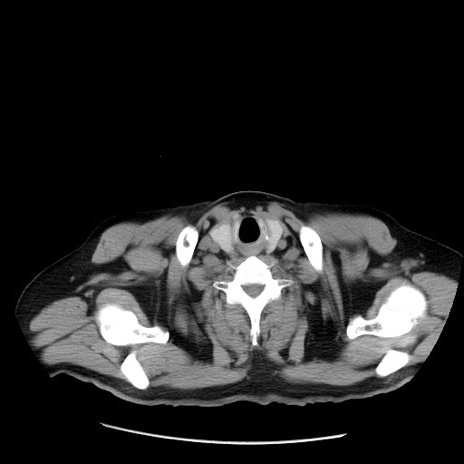

症例20(横断像)

【症例】 60歳代男性

【主訴】 腹部膨満、嘔吐

【現病歴】5日前頃より倦怠感を認め食事量減少し4日前の朝嘔吐、食事摂取困難となった。 3日前近医受診し点滴施行され整腸剤などを処方された。 当日他院を受診し、腹部膨満著明、炎症反応の上昇(CRP10.8、WBC11200)あり、紹介受診となる。

【身体所見】 意識JCS1 受け答えがはっきりしないBP 111/57mHg、 P 67bpm、、BT35.2°C、SpO2 97%(RA)、 腹部:膨隆、打診で鼓音あり、全体的に圧痛有り、腸蠕動音(-)、反跳痛ははっきりせず。

【データ】WBC 11400、CRP 14.20